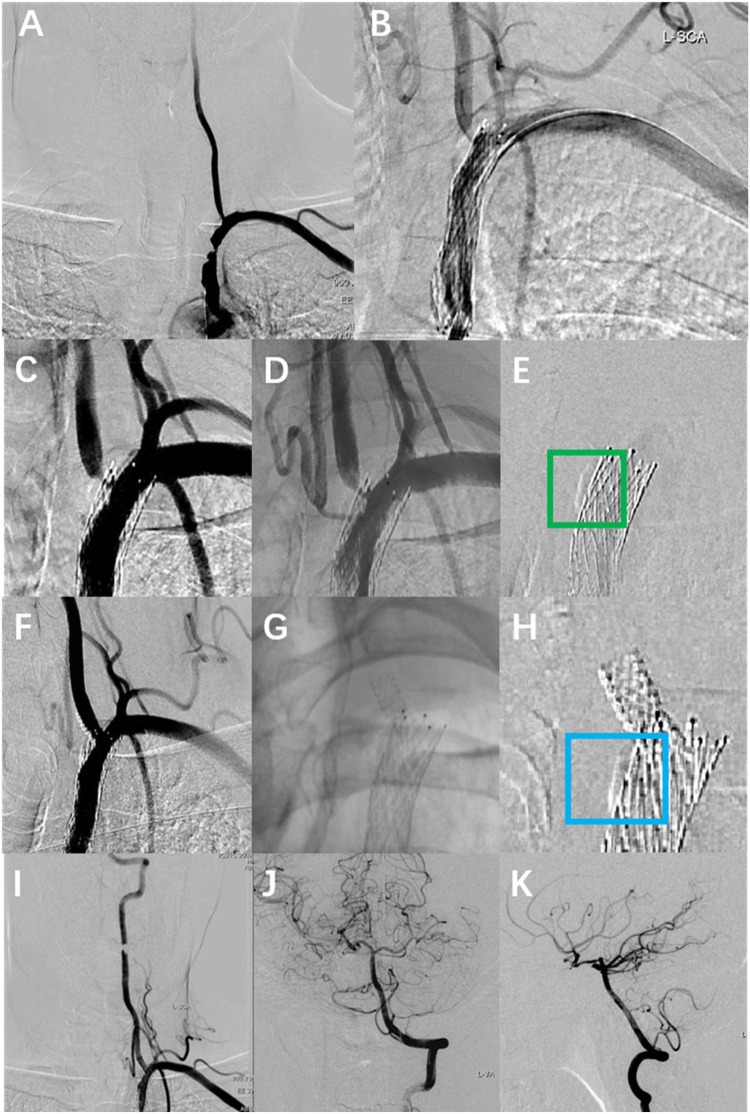

导言:支架骨折是一种公认但罕见的与椎动脉起源支架相关的并发症。方法:我们报告一位因眩晕和复视而被诊断为左椎动脉源性狭窄的男性患者,他使用了雷帕霉素洗脱支架。1年随访的计算机断层血管造影显示支架中部骨折伴远端碎片向V3节段迁移,但患者无症状,并在密切监测下进行医学治疗。结果:本病例说明雷帕霉素洗脱支架是治疗椎动脉起源狭窄的有效方法。讨论:在涉及支架完全骨折和远端碎片迁移的罕见病例中,保守治疗可能是无症状患者的可行选择。

Methods: We present a male who was diagnosed with left vertebral artery origin stenosis due to vertigo and diplopia, and who was deployed with a rapamycin-eluting stent. One-year follow-up computed tomography angiography demonstrated mid-stent fracture with distal fragment migration into the V3 segment, but the patient was asymptomatic and managed medically with close surveillance.